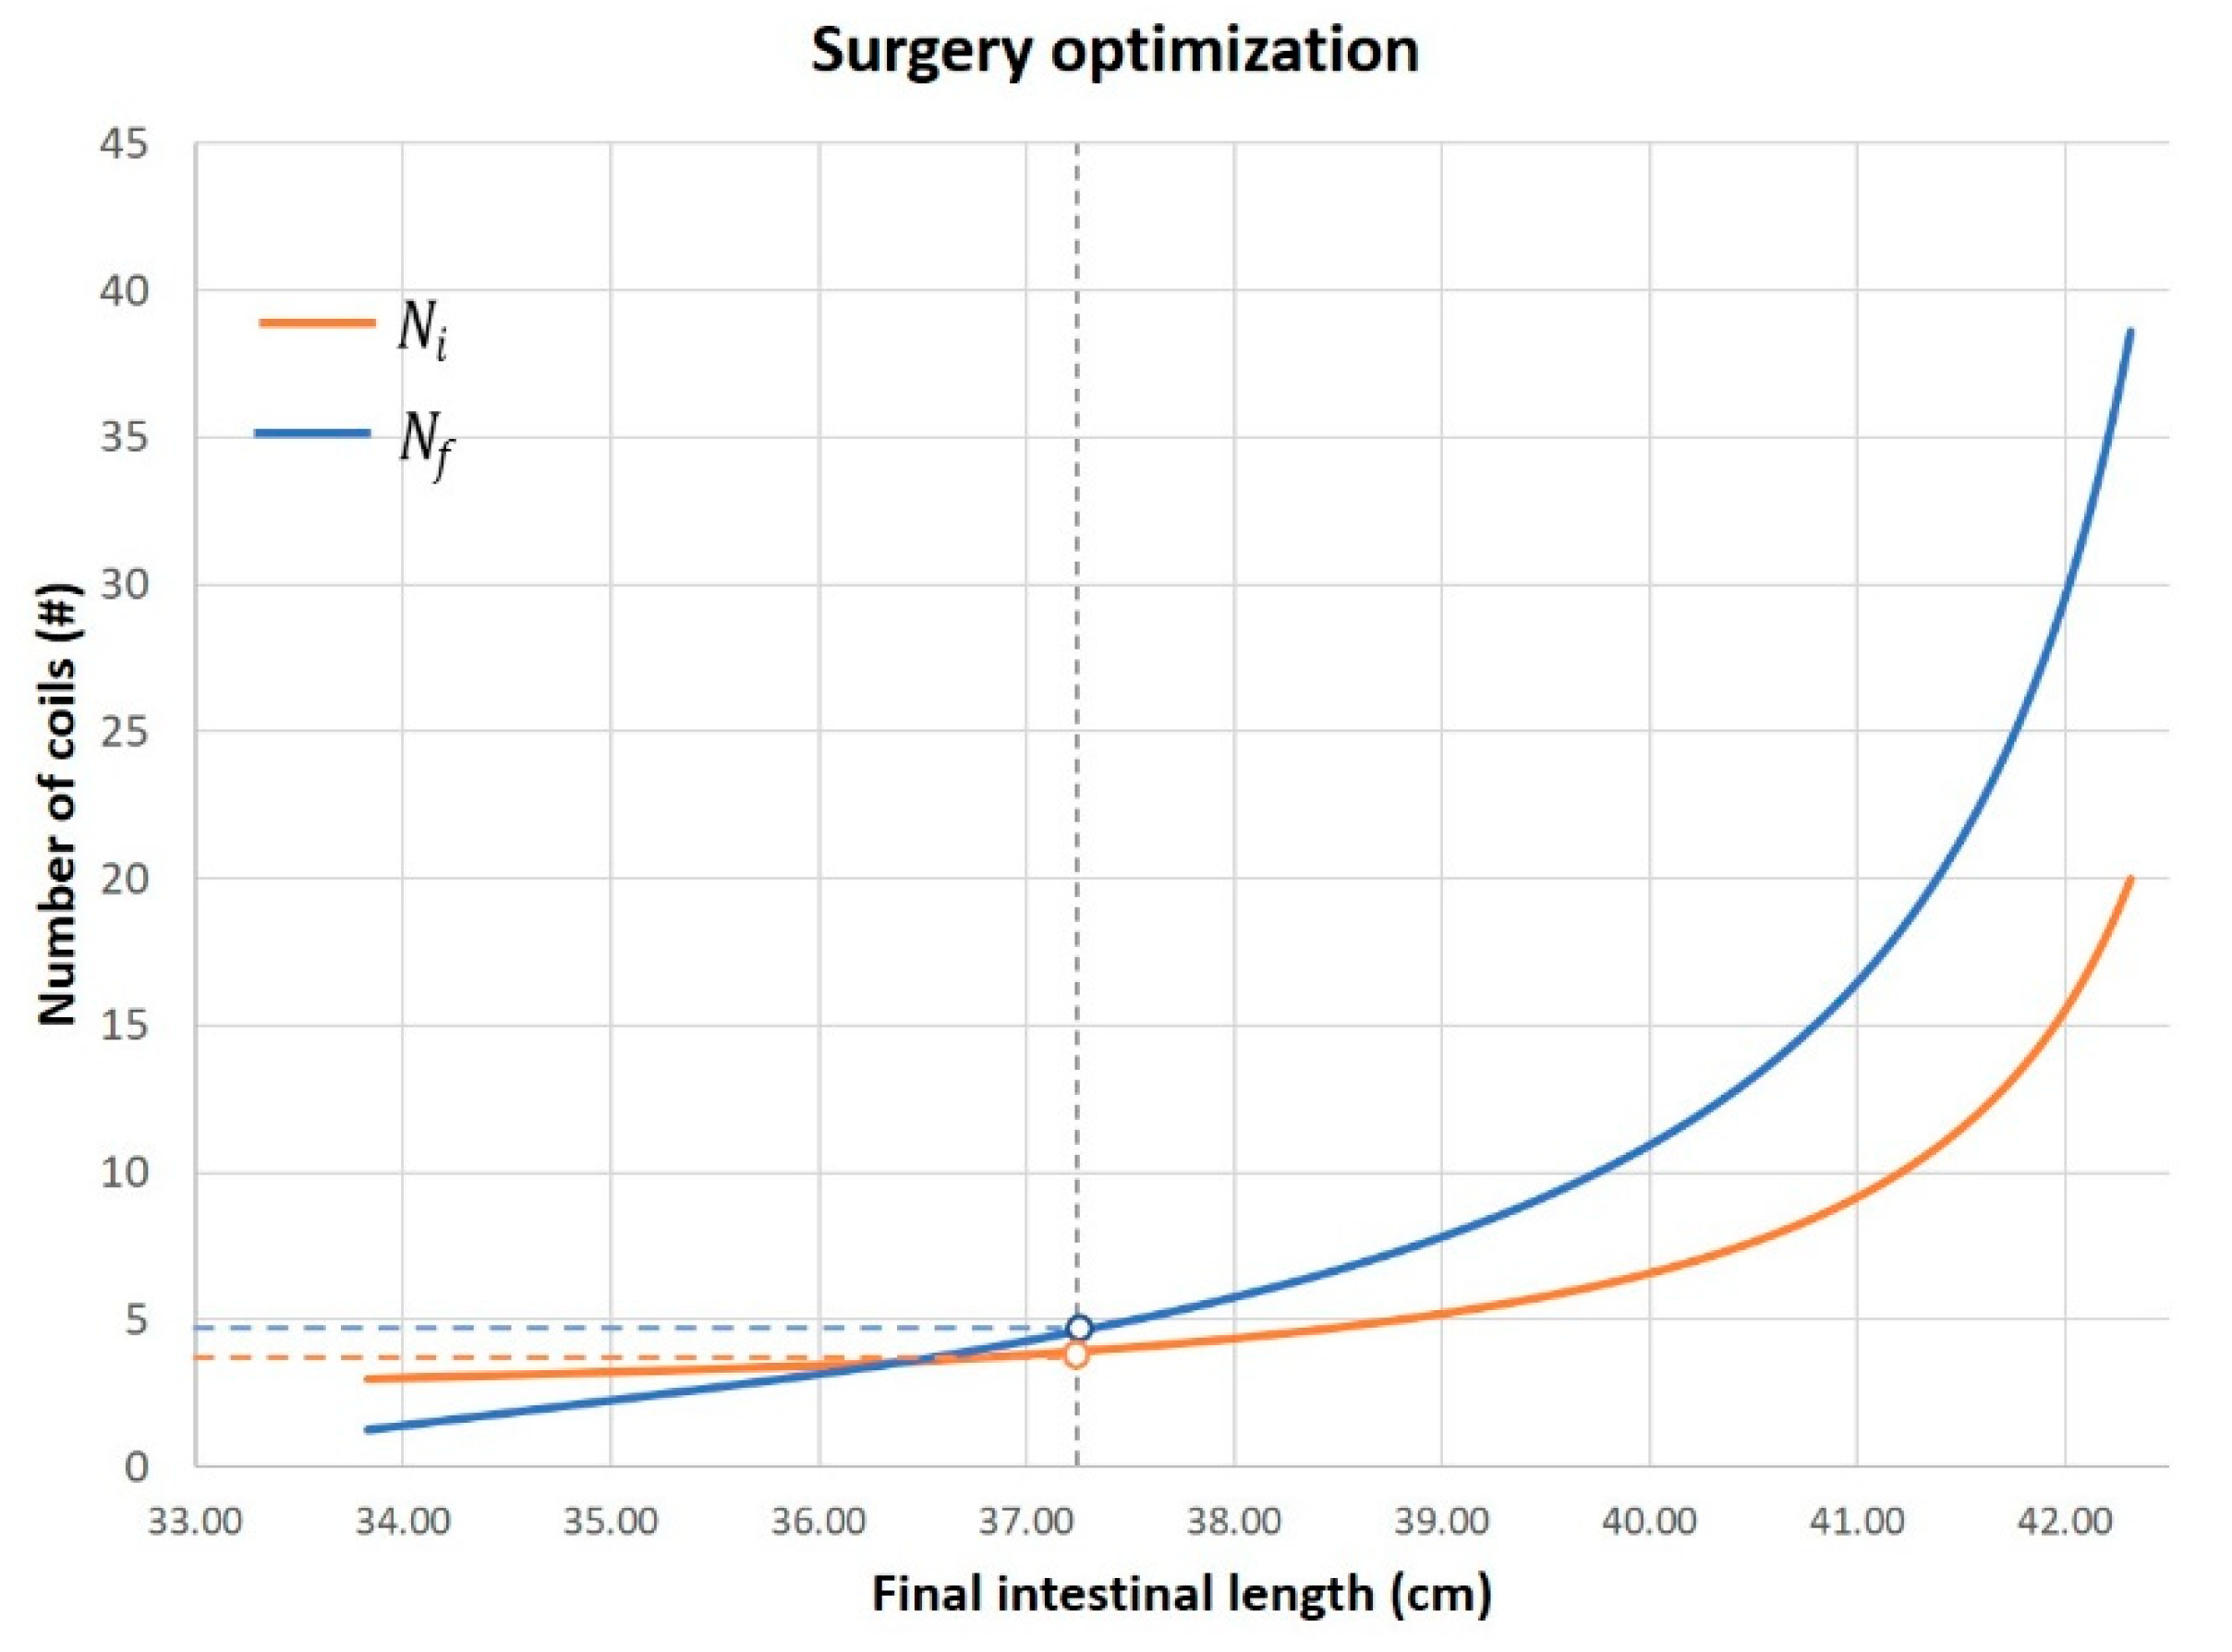

2.2. Surgical Feasibility

3. Results